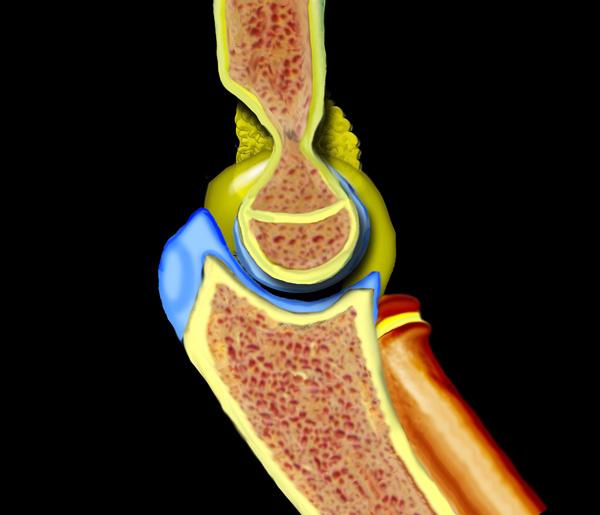

Chấn thương khớp khuỷu tay thường là kết quả của tình trạng duỗi quá mức hoặc vẹo ngoài quá mức do ngã chống tay ra phía trước.

Cuộn qua các hình ảnh ở bên trái để xem cách duỗi quá mức dẫn đến gãy xương trên lồi cầu.

Tình trạng tràn máu khớp sẽ dẫn đến sự dịch chuyển của đệm mỡ phía trước lên trên và đệm mỡ phía sau ra phía sau.